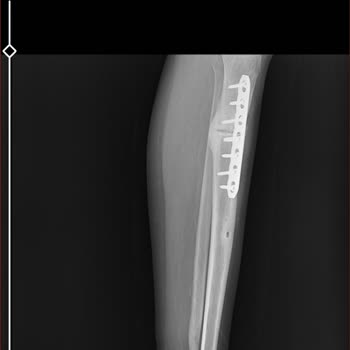

21 Ağustos 2025 tarihinde iş kazası sonucu ambulansla Antalya Medical Park Hastanesi’ne kaldırıldım. Kolumu cam kestiği için hastaneye gider gitmez film çektiler. Yarım saat sonra odada beklerken gelip doğrudan yarayı dikişle kapattılar. Dikiş atılırken doktorlara bileğimi hissetmediğimi ve oynatama...